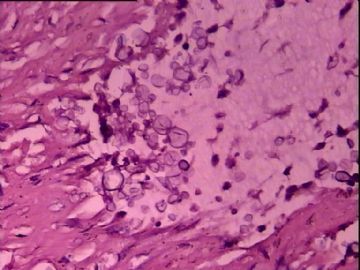

膀胱肿物

性别:

男

年龄:

46岁

标本名称:

简要病史:

肠梗阻入院

肉眼检查:

肿物位于膀胱尖部,腹膜外,约4x3cm,内含胶冻样物质,壁厚0.1-1.5cm。

图2